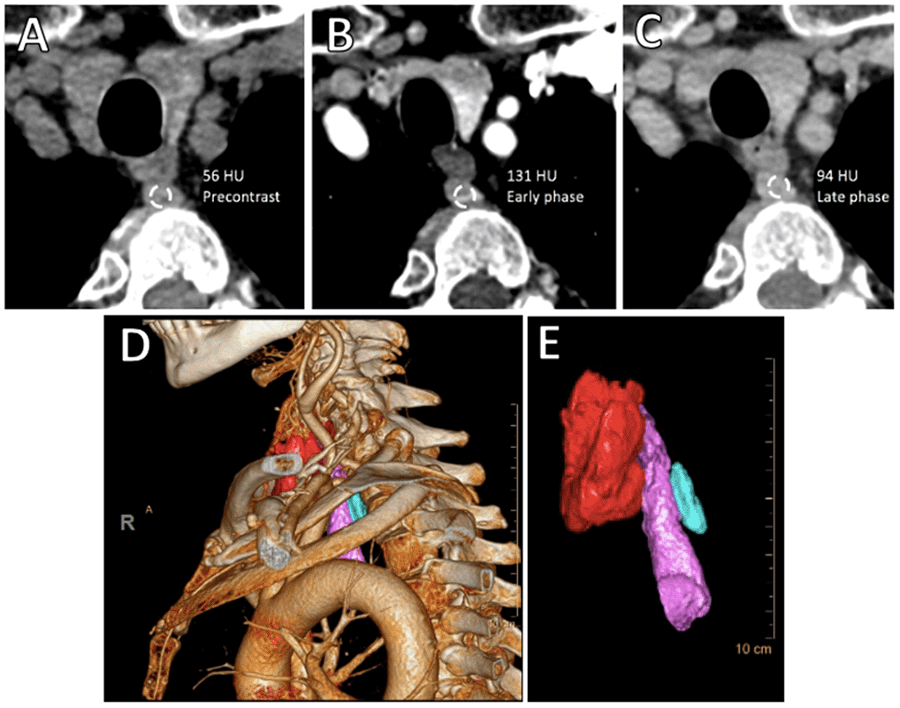

CT neck revealed an 11 × 12 × 21 mm mass posterior to the upper esophagus. This mass measured 56 Hounsfield units (HU) on non-contrast imaging, enhanced to 131 HU on arterial phase, and washed out to 94 HU on delayed imaging , a pattern suspicious for parathyroid adenoma (Figures 1A‒1C). Computer-aided 3D-CT reconstructed rendering images clearly demonstrated the enlarged retroesophageal parathyroid adenoma and its precise anatomic location (Figures 1D and 1E). Operative findings were identical to those predicted by the CT scan (Figure 2).

Figure 1. CT Scan of Neck and 3D-CT Reconstructed Rendering. Published With Permission

A) 11 × 12 × 21 mm mass measuring 56HU on non-contrast imaging was noted posterior to the upper esophagus, B) which enhanced to 131 HU on arterial phase, and C) washed out to 94 HU on late phase. D and E) 4D-CT rendering images demonstrated the enlarged retroesophageal mass (light blue mass; thyroid gland indicated in red, esophagus in lavender).

Four-dimensional parathyroid CT scans characterize parathyroid tissue based on its rapid contrast uptake and washout, differentiating it from lymphoid or thyroid tissue. Thus, a single scan can combine functional data with precise sectional anatomic detail, which may be reformatted into three-dimensional images using computer software (Figure 1B and C; the 4th dimension in "4D" refers to the timing of contrast uptake and excretion). While 4D-CT scans require slightly higher radiation exposure than conventional parathyroid imaging, their utility in localizing otherwise radiographically occult parathyroid adenomas is unquestioned. A study of 90 patients undergoing reoperative parathyroidectomy confirmed a high rate of concordance between 4D-CT imaging and surgical findings and correlated the 4D-CT group with a shorter operative time.8 In patients undergoing an initial operation for primary hyperparathyroidism but had non-localizing ultrasonography and sestamibi scans, studies have also shown that preoperative 4D-CT scan improves localization.9 A retrospective study by Hinson et al. demonstrated that 4D-CT localized parathyroid adenomas to the correct side with 84% sensitivity and 82% specificity in cases with non-localizing preoperative ultrasound and SPECT-CT scans.10